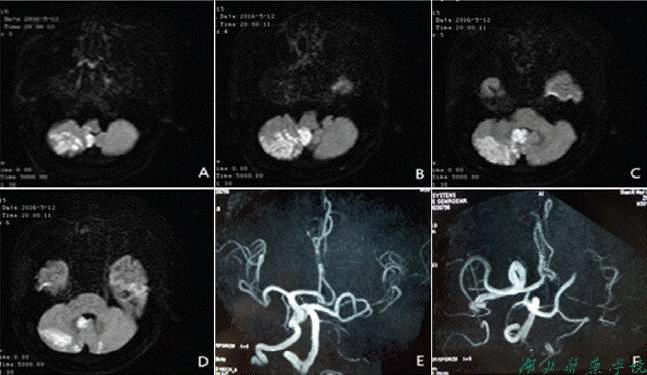

3.MRI诊断:多方位直接成像,显示结构无死角;可直接显示动脉瘤等血管异常;显示脑梗死时间更早;无需造影剂可直接行MRA。

图14 脑梗死MRI及DSA